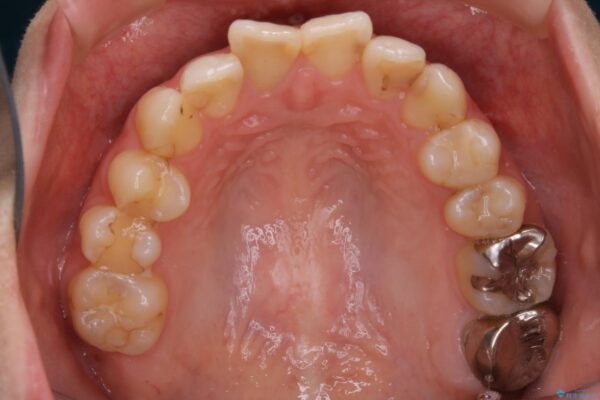

治療前

20代 女性 非抜歯で歯列をコンパクトに20代 女性 非抜歯で歯列をコンパクトに20代 女性 非抜歯で歯列をコンパクトに